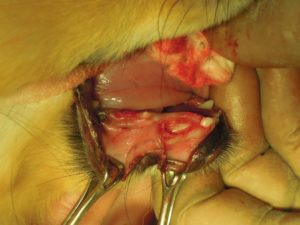

4.乳犬歯を抜歯して、歯肉を切除すると、永久犬歯が見えてきました。

5.周囲の骨を削り、犬歯を抜くスペースを作り

6.犬歯を抜歯してから、周囲の組織を切除して